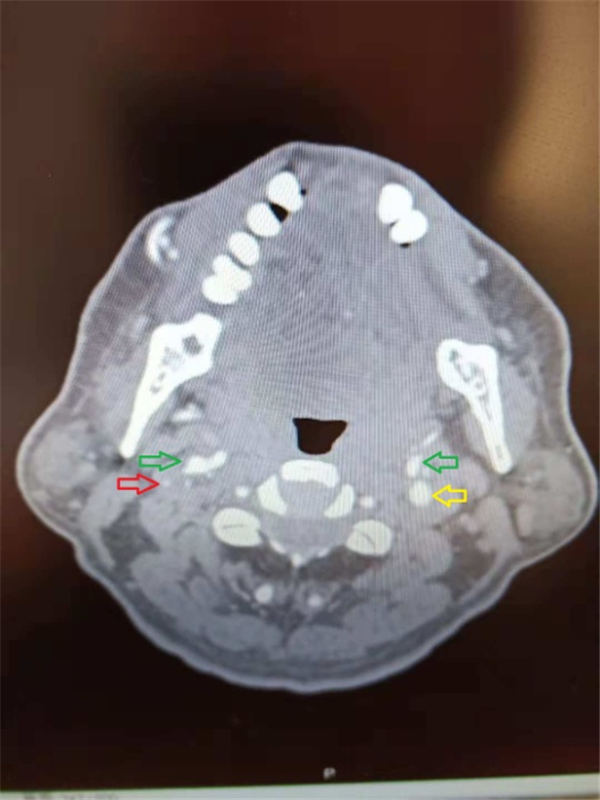

不过陈主任告诉老杜,他右侧的颈内动脉(上图红色箭头)由于粥样硬化斑块形成,和颈外动脉(上图绿色箭头)、左侧颈内动脉(上图黄色箭头)相比,已经有90%狭窄,基本接近闭塞了。动脉重度狭窄会严重影响脑部供血,造成脑供血不足、头晕,而狭窄部位的斑块如果脱落,则会导致脑梗塞,大范围的脑梗塞,甚至会危及生命。